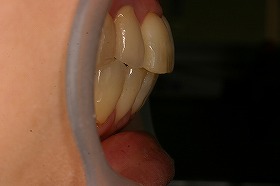

歯の矯正治療 症例ビフォー&アフター

ご覧の症例は前歯のねじれ出っ歯を矯正治療でキレイにし、

さらに、奥歯のぎらつく銀歯をセラミックにつめなおしたケースです。

今回の治療費 表側矯正治療全顎 装置費80万円+税 調整1回5000円+税 セラミック治療12本856,000円+税